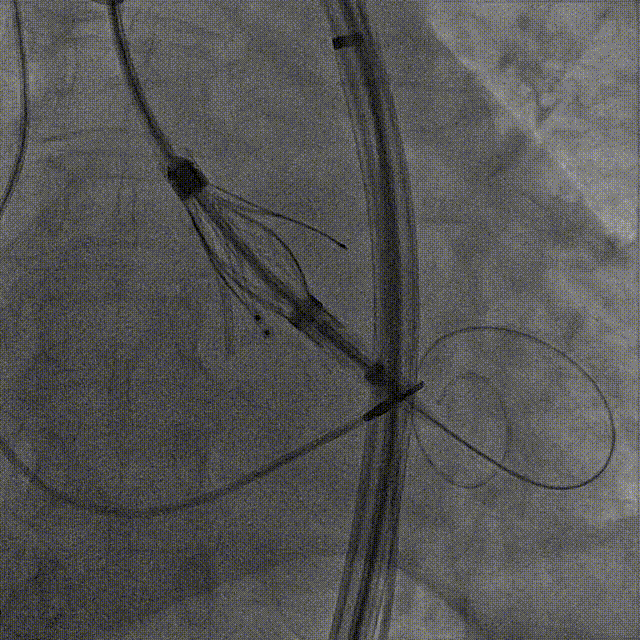

手术过程:5A 标准化流程SOP

右窦中心造影

大鞘到STJ

瓣膜调弯后解离

瓣膜右窦中心调整

定位键窦不对齐

灵活旋转操作

确认窦对齐

入窦

无窦超选验证

左窦超选验证

一键释放

术后造影